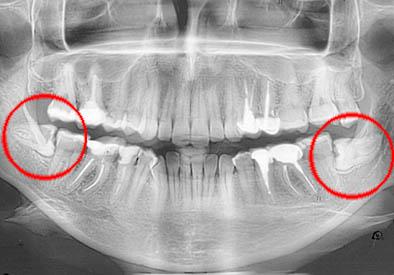

Ретинированным зубом мудрости называют своего рода аномалию зуба, располагающегося на 8 месте в ряду, а также являющегося третьим по счету моляром (большой коренной зуб). Суть данной аномалии заключается в том, что зуб мудрости не может прорезаться и занять отведенное для него место в челюсти. Вследствие этого зуб мудрости остается внутри кости или же немного прикрыт слизистой.

Причины возникновения ретинированных зубов могут быть разнообразными, но по статистике чаще всего ретенция зуба возникает вследствие раннего удаления молочных зубов в детстве или по причине неправильного расположения зубного ряда в челюсти, когда для прорезывающегося зуба просто нет места.